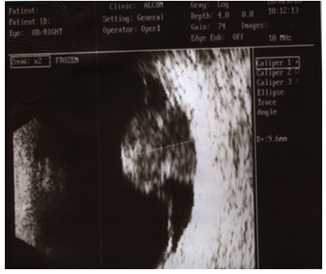

2. Ультразвуковое исследование - ведущий метод диагностики опухолей глаза. Методика проведения контактная и безболезненная. Сканирование позволяет «увидеть» опухоль при непрозрачных средах глаза, установить ее размеры.